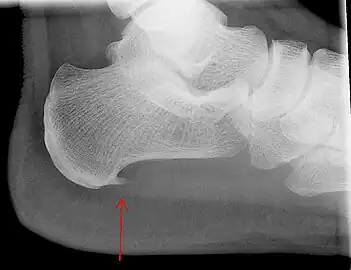

Heel bone with heel spur

An incidental finding associated with this condition is a heel spur, a small bony calcification on the calcaneus (heel bone), which can be found in up to 50% of those with plantar fasciitis.[6] In such cases, it is the underlying plantar fasciitis that produces the heel pain, and not the spur itself.[13] The condition is responsible for the creation of the spur though the clinical significance of heel spurs in plantar fasciitis remains unclear.[12]

Medical imaging is not routinely needed. It is expensive and does not typically change how plantar fasciitis is managed.[15] When the diagnosis is not clinically apparent, lateral view X-rays of the ankle are the recommended imaging modality to assess for other causes of heel pain, such as stress fractures or bone spur development.[7]